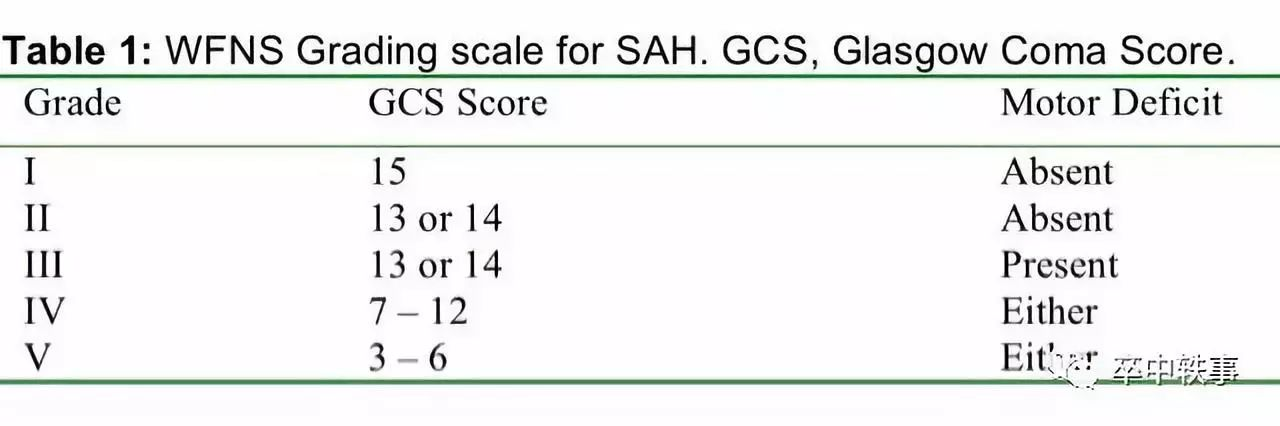

Drake 的另一个主要贡献是与 Graham M. Teasdale(1940-,见 Teasdale 一章),Neal Kassell,Keji Sano 等人一起在1988年提出蛛网膜下腔出血的 “世界神经外科联盟评分量表 - World Federation of Neurosurgical Society - WFNS SAH Grading Scale”(上图)。

发起和使用 WFNS 量表的原因是因为一项大型国际试验研究了68个国家的3521个蛛网膜下腔出血病人,发现两个因素可以推测预后。一是发病后意识障碍程度,与死亡率和致残率有关,二是有否出现偏瘫失语,只与致残率有关。